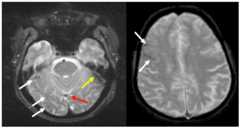

Figure 4. Conspicuity Depends on Technique. SWI vs T2* GRE.

SWI image (left) compared to T2* image of same patient on same day on the right. Note, there are 4 more MB detected on the SWI image